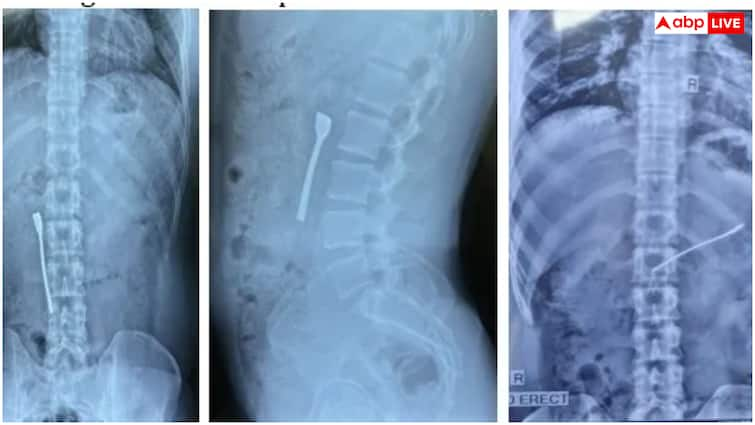

During June 2025, a 30-year-old man complained of severe stomach pain and not digesting food at a multi-spicy hospital in Delhi. He told that he swallowed steel spoon with water while taking medicines. This spoon was trapped in his upper intestine, causing him to have problems. During the investigation, the doctors saw that a teaspoon of 8 cm is stuck in the upper intestine of the patient. It was a very dangerous condition, because the metal object could cause holes in the intestine or serious infection. & Nbsp;

Doctors of Fortis Hospital gave emergency upper gastrointestinal (GI) endoscopy by giving anesthesia to the patient. A thin flexible tube endoscope was used in this process. This tube has a camera and light, which helps doctors to see the internal organ. The surgical team carefully took the spoon out of the intestine with the help of Foursep (Special Medical Tool). The patient’s intestine was not damaged while removing the spoon. Spoon was removed from the stomach in just 30 minutes. & Nbsp;